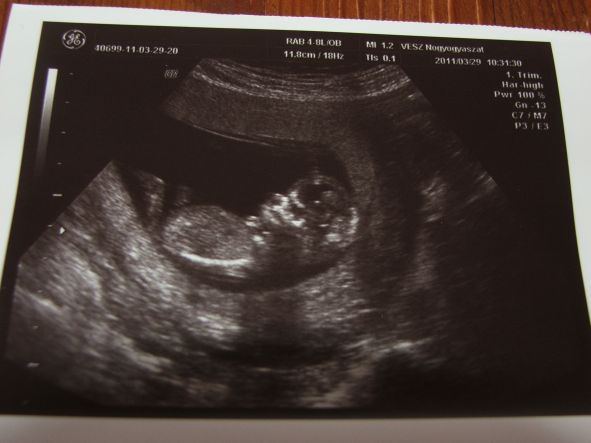

Kicsidodi, nem akarok amniót, csak most valahogy úgy rajtam van a félsz. Úgy döntöttem, hogy 2db 12. heti uh-ra megyek két különböző helyre, de csak a másodikon, azaz az Istenhegyinél csináltatok kombinált tesztet (integrálton is gondolkozom), az elsőnél "csak" uh. Az első uh-s dokim is rajta van a listán, amit a rózsakertieknél láttam, mint a Fetal Medicine hálózat dokija down-szűrésre. Bízom benne, hogy most sem lesz semmi gond, ahogy az előző srácaimnál sem. Ráadásul én nagy uh-kra járó vagyok, tehát lesz többször 4d, ha van valami, ennyiből ki kellene derülnie - ezzel nyugtatgatom magam